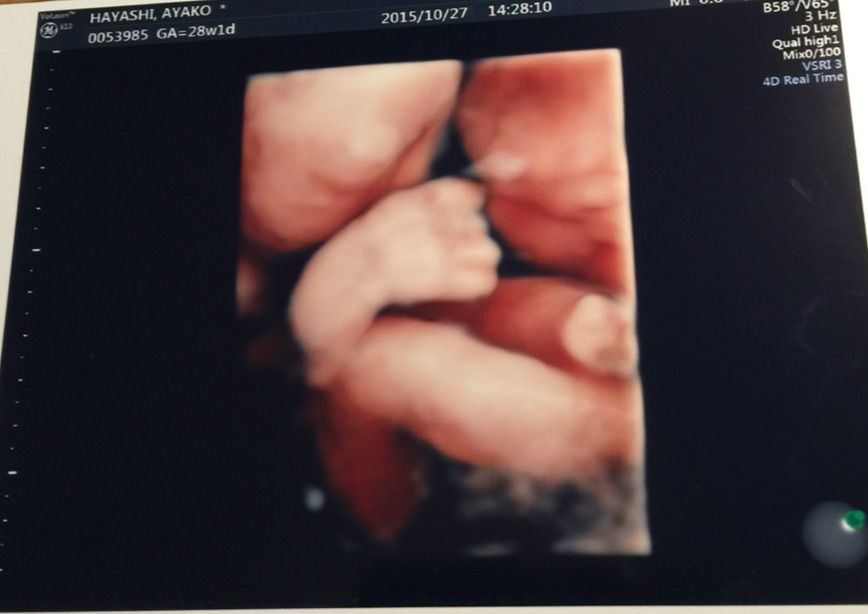

…って事で、昨日は撮影後に4Dエコーなるものを見る為に妻と病院へ。

結構動いてたので手足が邪魔して見えなくなったりしましたが…

手も足も元気な証拠かな?とか思いつつ、右手の指がなんとなく5本確認できたのでハサミは握れるな!とかも密かに思ったりしてました( ^ω^ )